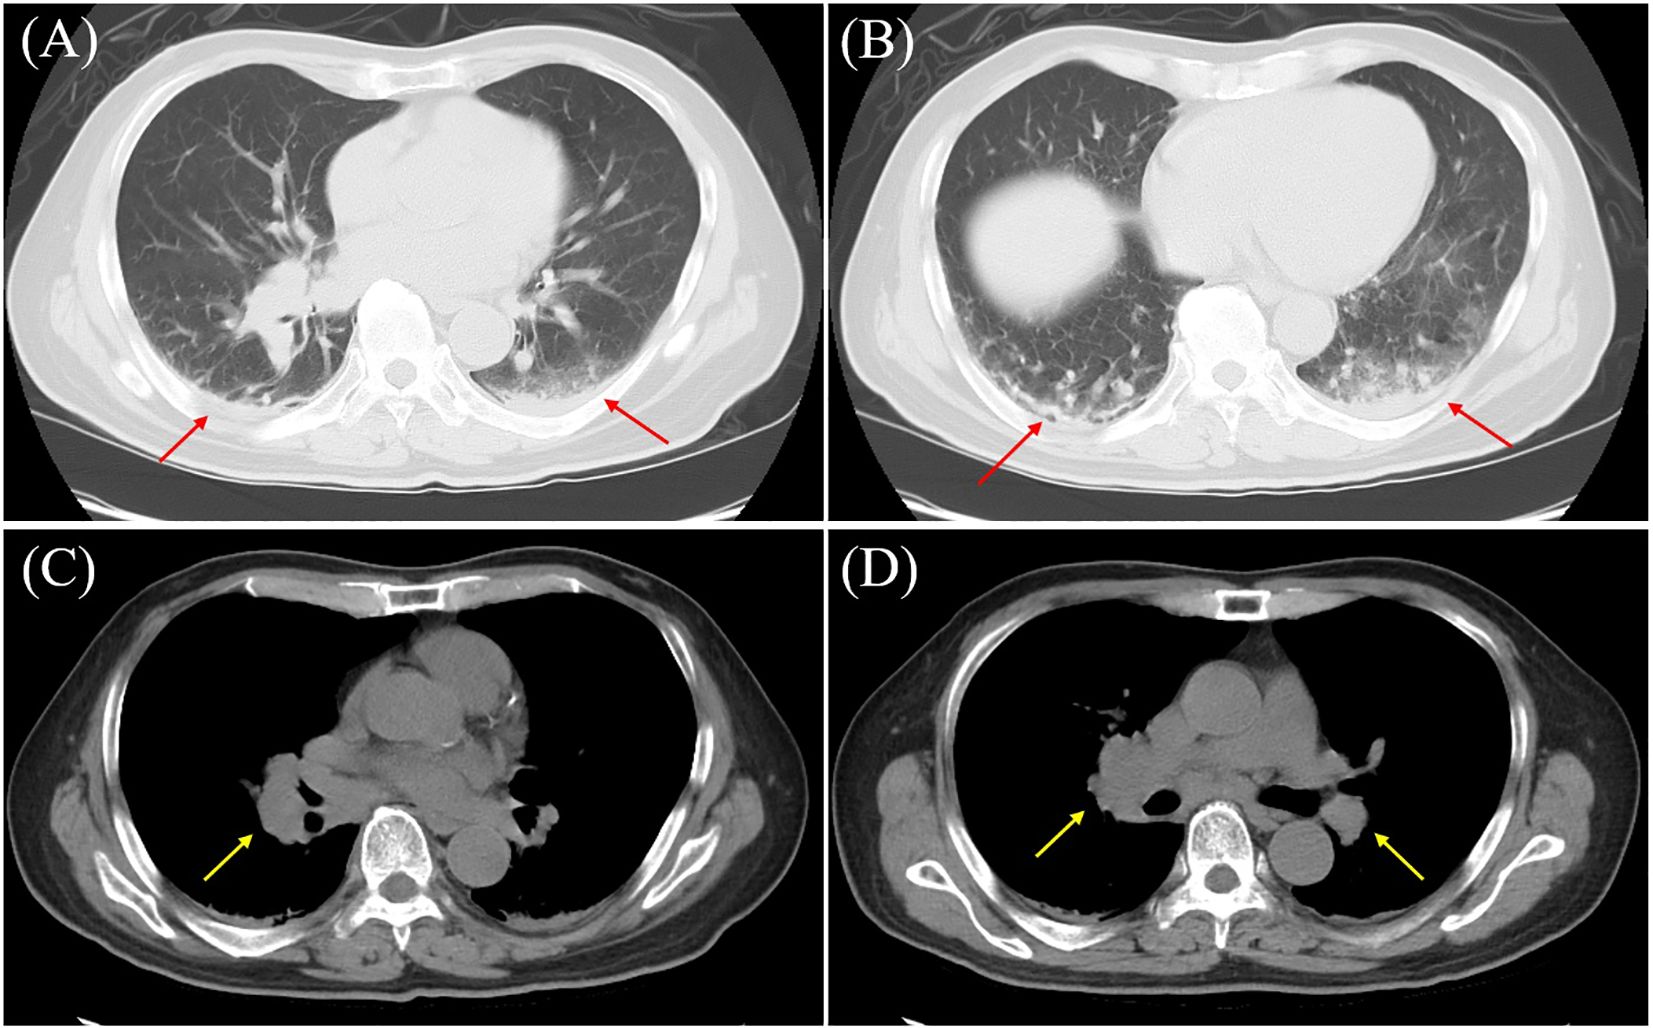

A 69-year-old man with a history of schizophrenia since age 47 (over two decades), who had been institutionalized in a psychiatric hospital, presented with generalized seizures lasting five minutes after a one-day history of fever and altered mental status. He had a history of smoking 10 cigarettes per day (though its duration was unknown) and had no prior history of epilepsy. Initial blood tests revealed a mild elevation of C-reactive protein (CRP 1.0 mg/dL), hyponatremia (Na 125 mEq/L), and a markedly elevated creatine kinase (CK 3000 U/L). Chest computed tomography (CT) showed infiltrative opacities consistent with pneumonia and hilar lymphadenopathy (Figure 1). Brain magnetic resonance imaging (MRI) was unremarkable on diffusion-weighted imaging (DWI).

Figure 1

Chest computed tomography (CT) findings. Chest CT showing infiltration in the dorsal basal segment of the lower lobe (arrows), indicative of aspiration pneumonia (A, B), along with mediastinal lymphadenopathy (arrows) (C, D). (A, B) Lung window; (C, D) mediastinal window.